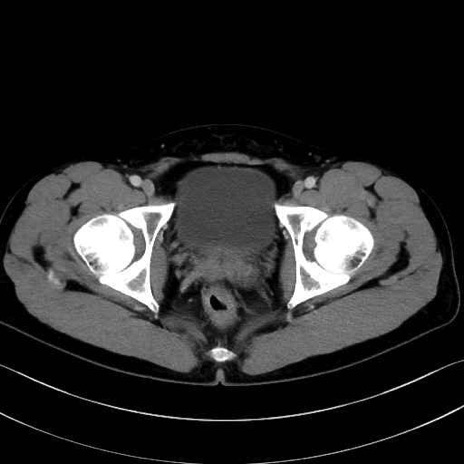

肛門挙筋(levator ani muscle)のCT画像の解剖

肛門挙筋 (Levator ani)